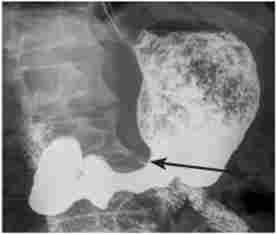

Зі спеціальних методів діагностики раку з виразки вельми інформативними виявляються променеві (рис. 12.7). Зокрема, до рентгенологічних ознаками малігнізації виразки відносяться:

У озлокачествівшейся виразці шлунка рентгенологічно може відзначатися дефект наповнення з трансформацією виразкового вала по ширині і з асиметрією у вигляді неправильної (трапецієподібної) форми з високими, подритимі нерівними краями.

Рентгенологічна картина пухлинного процесу при виразці шлунка

Мал. 12.7. Рентгенологічна картина пухлинного процесу при виразці шлунка